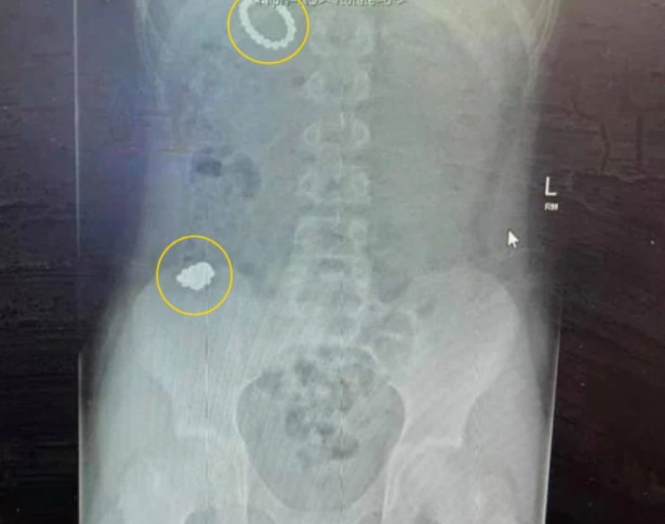

Una radiografía reveló que había muchos más que eso y, temiendo que pudieran quemar sus órganos y matarlo, lo llevaron de urgencia a cirugía para una operación de seis horas.